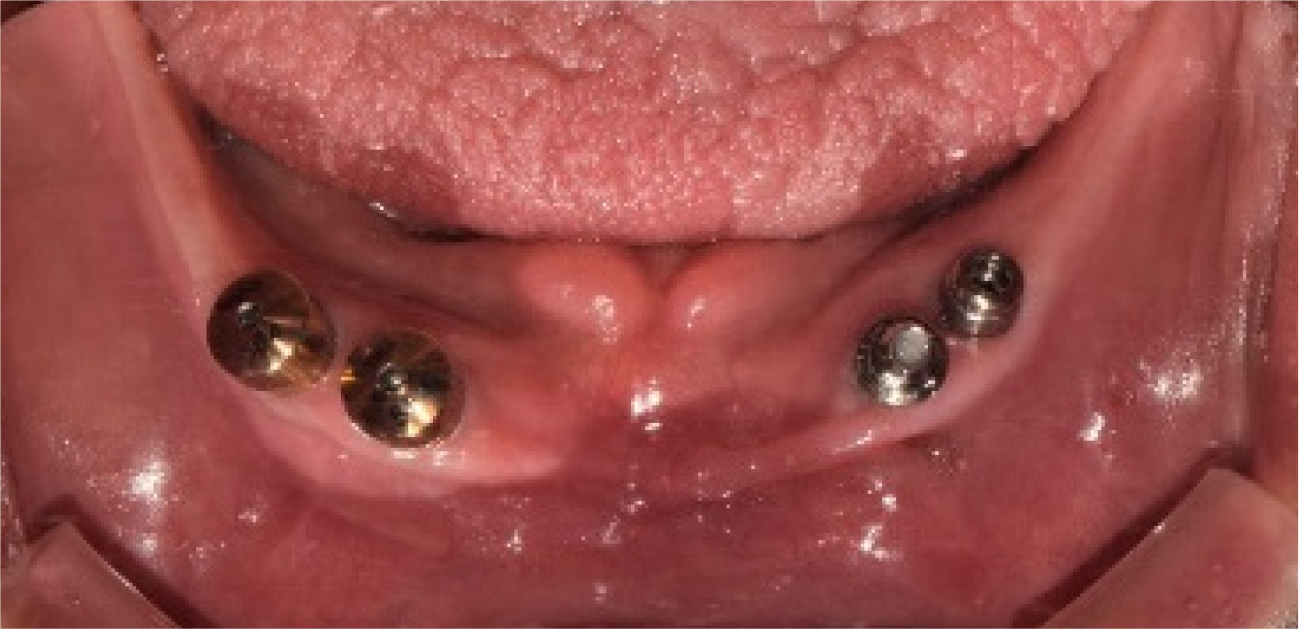

The FDP in the anterior area of the maxilla and the full-arch FDP in the mandible were removed, and the hopeless implants were removed under local anesthesia. After three months of healing (Fig. 4), when the gingiva and underlying bone stabilized, prosthetic treatment commenced. a six-unit metal ceramic FDP was fabricated in the maxilla using conventional silicone impression and casting procedures. In the mandible, pick-up impression taking was performed for the four remaining implants using an individual tray and silicone materials (Aquasil Ultra LV; Dentsply Sinora, Philadelphia, PA, USA) (Fig. 5). Inner crowns with a 2° convergence angle and a chamfer margin were fabricated for the four implant fixtures with Co-Cr alloy (VeraBond 2V; Aalbadent, Fairfield, CT, USA) (Fig. 6). The corresponding outer crowns were fabricated and attached to the metal framework of the denture using a laser welding technique. Afterwards, fabric pins with the diameter of 0.8 mm were placed on the outer crowns using the spark erosion technique. The vertical dimension of the occlusion was established considering esthetics and function. Artificial teeth (Endura; Shofu, Kyoto, Japan) were arranged using the group function concept and a wax denture was created (Fig. 7). After confirming the wax denture in the oral cavity, a definitive prosthesis was fabricated using flasking, wax wash, and resin packing procedures (Fig. 8).

Periodic recall checks were done every three months after the delivery of the definitive prosthesis. During the three year follow-up period, no periodontal or prosthetic complications were observed (Fig. 9). The patient was satisfied with the ease of hygienic care for the definitive prosthesis, and the implants were well maintained.